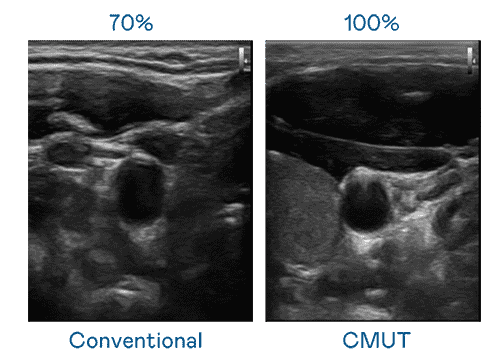

CMUT 技术是一种用电容式微机电元件来产生超音波讯号的技术。。。与传统 PZT 压电式技术相比,,,CMUT 频宽增加 30%,,,更宽频的超音波讯号让影像解析度大幅提升,,是实现高影像品质医疗超音波扫描、、、、促进精准医疗发展的关键技术。。。

超音波影像的解析度高低,,首先取决于探头能发出的讯号频宽。。。28国际 CMUT 可提供高清晰的超音波讯号,,,提供高频宽、、高灵敏度、、、影像纹理细节更高的超音波影像,,,,协助医护人员缩短影像判读时间及利用精准的医疗影像进行诊断。。。